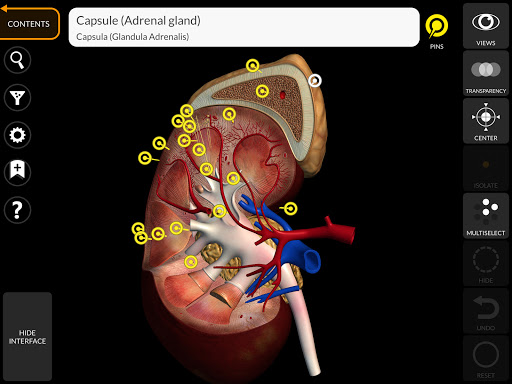

"Anatomy 3D Atlas" cho phép bạn nghiên cứu giải phẫu người theo cách dễ dàng và tương tác.

Thông qua giao diện đơn giản và trực quan, bạn có thể quan sát mọi cấu trúc giải phẫu từ mọi góc độ.

Các mô hình giải phẫu 3D đặc biệt chi tiết và có kết cấu lên đến độ phân giải 4k.

Việc phân chia theo vùng và chế độ xem được xác định trước giúp quan sát và nghiên cứu các bộ phận hoặc nhóm hệ thống riêng lẻ và mối quan hệ giữa các cơ quan khác nhau.

MÔ HÌNH GIẢI PHẪU 3D

• Hệ thống nội tiết • Hệ thống